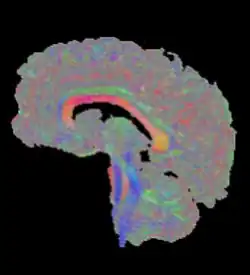

Außerdem wird die Richtung des größten Diffusionskoeffizienten häufig als Farbwert kodiert. Hierbei wird jeder der drei Achsen eine der Grundfarben rot, grün und blau zugeordnet, die bei dazwischen liegenden Richtungen gemischt werden.[4] Voxel ohne klare Hauptrichtung erscheinen grau (siehe Abbildung).

Als Traktografie oder Fiber Tracking werden Verfahren bezeichnet, die den Verlauf größerer Nervenfaserbündel rekonstruieren. Zur Visualisierung sind hierbei Darstellungen von Hyperstromlinien üblich, dreidimensionalen Linien, deren Verlauf der Richtung des größten Diffusionskoeffizienten folgt.[5][6] Die Abbildung am Beginn dieses Artikels zeigt beispielhaft alle Bündel, die die Medianebene schneiden. Einen alternativen Ansatz stellt die probabilistische Traktografie dar. Sie berechnet für jeden Punkt im Gehirn eine Wahrscheinlichkeit, mit der auf Grundlage der Daten eine Nervenverbindung mit einem gegebenen Ausgangsareal angenommen werden kann.[7] Derartige Ergebnisse eignen sich weniger für die Erzeugung aussagekräftiger Bilder, ermöglichen jedoch quantitative Aussagen und finden daher in der Kognitionsforschung Verwendung.